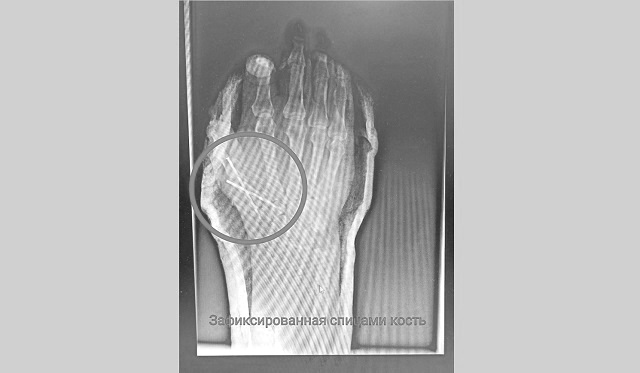

В  экстренном порядке мужчину прооперировали. Травма оказалась сложной, мужчина мог лишиться большого пальца, который почти полностью был отрезан от  руки. Врач восстановил сначала пястную кость, зафиксировав ее  спицами, потом аккуратно восстановил сухожилия. Операция продлилась 2,5 часа.

Фото: пресс-служба НЦРМБ